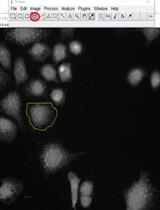

Live-cell fluorescence resonance energy transfer (FRET) assays in combination with microscopy and digital imaging technologies are commonly used to monitor the kinetics with which levels of cAMP and Ca2+ fluctuate in response to GPCR agonist stimulation. Here, we report an alternative approach that does not use microscopy but that instead enables FRET-based detection of cAMP and Ca2+ in a 96-well format using an automated microspectrofluorimeter and monolayers or suspensions of living cells. The protocol uses genetically encoded biosensors so that averaged kinetic data for pharmacological studies can be obtained in real time using a microplate reader under conditions in which GPCR agonists are applied at known concentrations. These FRET assays use cell lines stably expressing the cAMP biosensor H188 (Klarenbeek et al., 2015) or the Ca2+ biosensor YC3.60 (Nagai et al., 2004), both of which exhibit superior dynamic range in comparison to earlier FRET reporters. Our protocol describes how H188 or YC3.60 can be expressed stably with recombinant GPCRs so that precise dose-response analysis is achievable. This protocol builds on our published studies, whereby novel dual agonist and triagonist properties of synthetic GPCR agonist peptides (e.g., EP45 and GGP817) were discovered (Chepurny et al., 2018 and 2019).

Using the genetically encoded biosensor Epac1-camps (Nikolaev et al., 2004), we were the first to develop a 96-well microplate FRET assay in which fluctuations of [cAMP] were monitored in monolayers of living cells in real time using a microspectrofluorimeter (FlexStation 3, Molecular Devices) (Chepurny et al., 2009). More recently, we have optimized this approach for purposes of drug discovery in a high-throughput mode. The major technical advance concerns our use of H188 and YC3.60, both of which we find to be highly responsive to cAMP and Ca2+, respectively. Importantly, our plate reader FRET assays using H188 or YC3.60 require their high-level expression, either by stable transfection to generate clonal cell lines (Chepurny et al., 2018), or by adenoviral transduction of cell lines (Chepurny et al., 2018 and 2019). Transient transfection is not useful since low-level expression of these biosensors is not compatible with the limited light detection limits of available microplate readers.

We have also created doubly-transfected HEK293 cells lines that stably express H188 or YC3.60 along with recombinant GPCRs of interest. These GPCRs include glucagon, glucagon-like peptide-1 (GLP-1), glucose-dependent insulinotropic peptide (GIP), peptide YY (PYY), corticotropin releasing hormone (CRH), and cholecystokinin (CCK) receptors. It is also possible to perform such FRET assays using HEK293 cells that stably express H188 or YC3.60, but are instead transiently transfected with a GPCR. Conversely it is possible to use a cell line that stably expresses a recombinant GPCR so that cells may then be virally transduced with H188 or YC3.60.